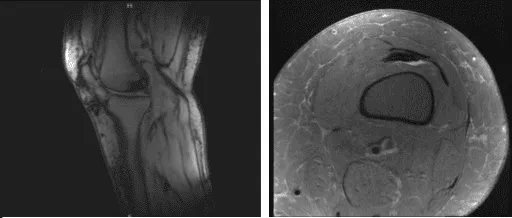

Los resultados de las radiografías presentados y revisados mostraron que no existen enfermedades degenerativas. Aconsejaron al paciente que se sometiera a una resonancia magnética y descubrí que hay edema subcutáneo tanto anterior como anteromedial.

Sospecha de desgarro en el cuerno posterior del menisco medial. Hay una señal oblicua muy tenue que parece extenderse hasta la superficie articular inferior. Se observó una ruptura parcial del LCP proximal y también se observaron condromalacia leve de rótula y bursitis infrapatelara profunda.

MRI-3T Rodilla Izquierda sin contraste